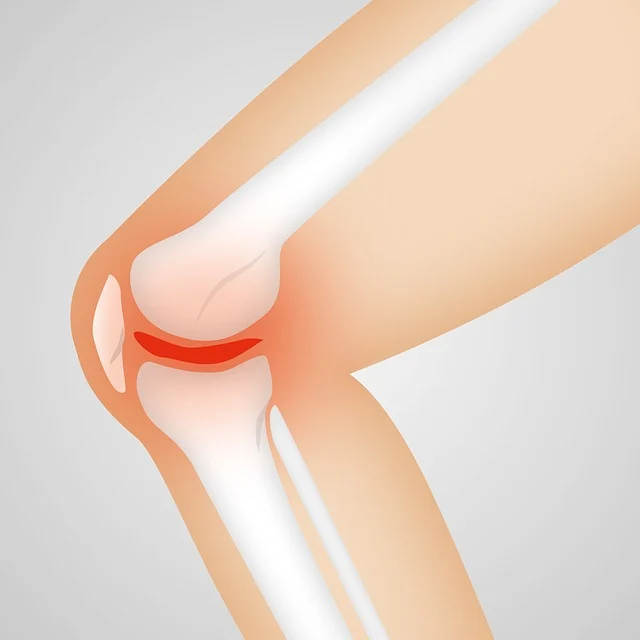

연골은 시간이 지나면서 자연스럽게 마모되고 퇴화됩니다. 콘드로이친은 연골을 재생시키고 강화하는 데 도움을 줍니다. 따라서 관절의 유연성과 움직임을 높이는 데 중요한 역할을 합니다. 고령층, 무릎이나 엉덩이 관절에 부담이 많은 사람에게 매우 유익한 성분입니다.

3️⃣ 염증 완화 및 통증 완화

콘드로이친은 관절 내 염증을 완화하고, 통증을 줄여주는 효과도 있습니다. 염증 감소와 수분 공급을 통해 관절을 더욱 건강하게 유지하는 데 도움을 줍니다. 이로 인해 장기적인 관절 기능 개선에 기여합니다.